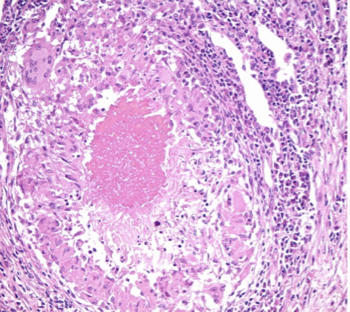

How do abscesses and cellulitis present histologically?

Abscess —> Well demarcated accumulations of neutrophils and/or necrotic debris

Cellulitis —> Poorly demarcated extensive neutrophilic to pyogranulomatous dermal and subcut inflam

Which aetiological agent causes skin granuloma (granulomatous dermatitis)?

Actinomycetes (Actinomyces and Nocardia) and Mycobacterium

What are the features of skin granuloma?

All animals

Grow slowly

Colonisation of bacteria of deeper skin part (opportunistic)

How does skin granuloma present grossly?

Identical to abscesses and cellulitis (distinguishable only via histology)

How do skin granulomas present histologically? Difference between pyogranuloma and granuloma

Pyogranulomatous dermatitis and panniculitis with bacteria embedded within Splendore hoeppli material (actinomyces, nocardia)

Granulomatous to pyogranulomatous dermatitis with central caseous necrosis (Myobacterium = ZN stain to identify)